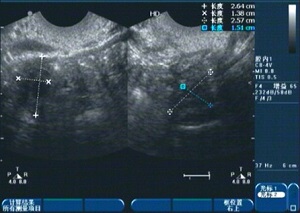

1、诊断:医生会通过询问病史、体检及辅助检查(如超声检查、激素检测等)来确定诊断。